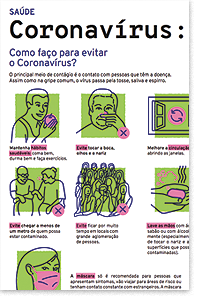

Como prevenir a contaminação por coronavírus

- Lavar as mãos com frequência/ ou utilizar álcool 70%, principalmente antes de consumir algum alimento;

- Utilizar lenço descartável para higiene nasal;

- Cobrir nariz e boca quando espirrar ou tossir;

- Evitar tocar mucosas de olhos, nariz e boca, higienizar as mãos após tossir ou espirrar;

- Não compartilhar objetos de uso pessoal, como talheres, pratos, copos ou garrafas;

- Manter ambientes bem ventilados, evitar contato próximo com pessoas que apresentem sinais ou sintomas da doença;

- Evitar contato próximo com animais selvagens e animais doentes em fazendas ou criações;

- Pessoas com sintomas de infecção respiratória aguda devem praticar etiqueta respiratória (cobrir a boca e nariz ao tossir e espirrar, preferencialmente com lenços descartáveis, e depois lavar as mãos).